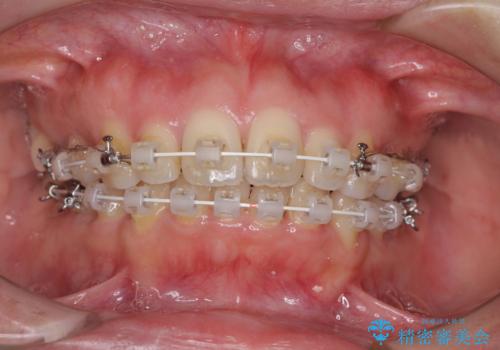

- 審美装置

- 前歯のデコボコと口元の突出感を気にして来院された患者様です。

上下左右第一小臼歯4本を抜歯し、ワイヤー装置にて口元を引っ込めるよう矯正治療を行うこととしました。

叢生が強かったため、口元の突出感の改善には限界がありましたが、横側からも口元が引っ込んだ感じが分かるほど改善されました。